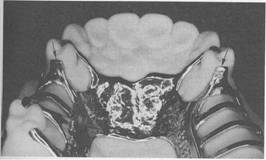

Fig. 5-34 Maxillary Class I partial denture frame­work with anatomic replica palatal major connector. Although retention is increased by using broad major connector, need for indirect retainers still exists, and they are placed on mesio-occlusal surfaces of first premolars. Direct retention is furnished by bar-type clasps engaging distobuccal undercuts on second premolars. Metal extension from framework contacts prepared guiding planes on distal surfaces of second premolars to complete clasp assembly.